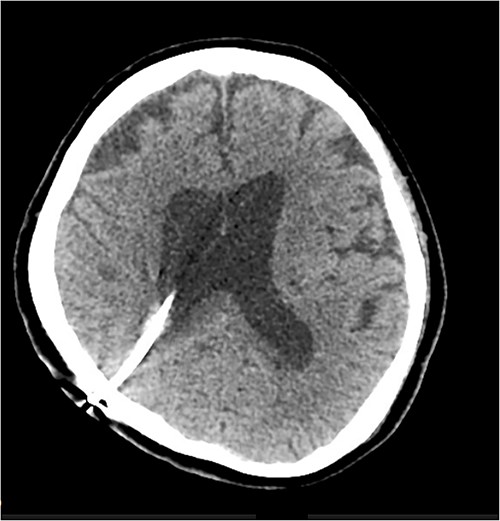

A 67 year-old woman was admitted to our service from the neurosurgical department for rehabilitation after a spontaneous left basal ganglia haemorrhage and diffuse intraventricular haemorrhage with hydrocephalus. She had been initially found unresponsive at home with coffee ground vomitus and incontinence of urine. An urgent computed tomography (CT) scan of the brain showed a large intracranial haemorrhage with intraventricular bleeding and hydrocephalus (Fig. 1). Her acute admission involved an extraventricular drain inserted by the neurosurgery service. A repeat CT brain performed 10 days later showed stable multicompartmental haemorrhage, and the extraventricular drain was removed. A ventriculoperitoneal shunt was inserted on Day 27 for ongoing management of the hydrocephalus. A digital subtraction angiogram showed no underlying aneurysm or arteriovenous shunt.

Initial CT revealing acute left-sided intraparenchymal haemorrhage with intraventricular extension and mass effect.